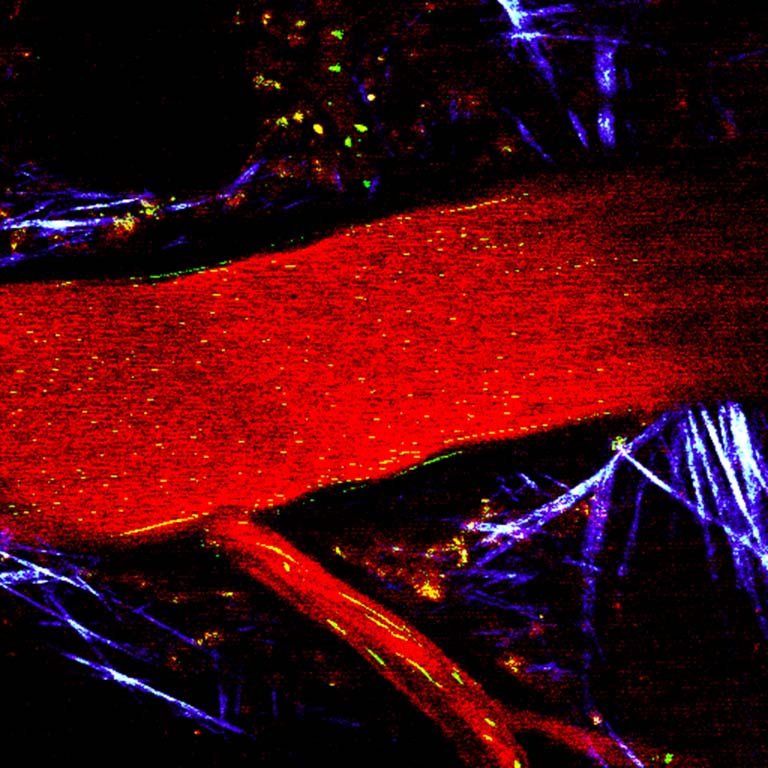

The images show a typical vascularized tumor tissue with cancer cells (unlabeled), collagen matrix (purple/white) and blood vessels (red). A novel strategy to fight cancer is to use tumor-seeking bacteria that can be modified to produce and release cancer toxins. A certain type of bacteria can even produce little magnetic particles in their body that make them respond to external magnetic fields, and also allow us to track them in the body using MRI. We study how such living therapeutic microorganisms (green/yellow) move in these vessels and how we can help them go deeper into the tissue using dynamic magnetic fields to make therapy become more effective.